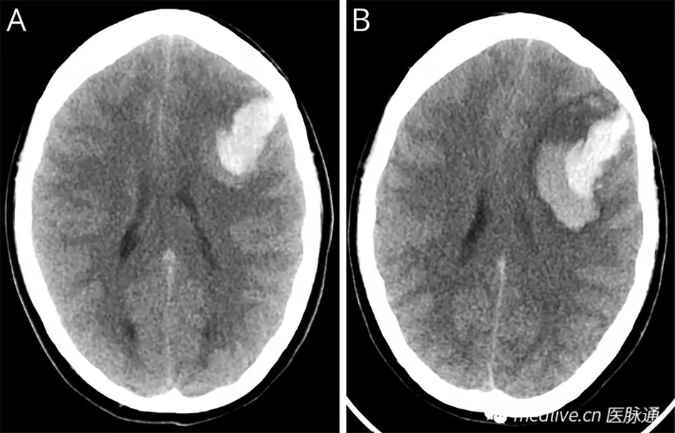

体格检查显示,患者清醒且反应良好。NIHSS评分为15分(因偏瘫和失语),格拉斯哥昏迷量表(GCS)评分为14分。血压在正常范围内。初始头部CT显示左额叶脑出血(ICH)(图1A)。

图1 头颅计算机断层扫描(CT)

患者开始呕吐

,意识水平迅速恶化至GCS评分12分。急性期CT扫描显示血肿扩大,血肿周围水肿

,中线移位增加(图1B)。随后进行了急诊开颅血肿清除术。